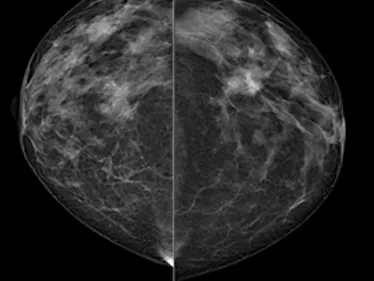

This mammography training aims to give a thorough overview of different mammography-based techniques like tomosynthesis, contrast-enhanced mammography, synthetic view and breast intervention. In addition to fundamental technical considerations, state of the art and indications of each technique will be provided. Theoretical lectures will be enhanced by interactive case demonstrations.

Everyday and complicated or rare cases will help participants to become familiar with the semiology of this modality, as well as technical issues, artefacts, and pitfalls. Indications and contraindications of mammography is also very important knowledge in order to best use these methods. Special issues on intervention under mammo/tomo/CEM and BI-RADS lexicon, would also be discussed.

- Provide up-to-date reviews on the technique and use of mammography, tomosynthesis and contrast enhancement

- Indications and clinical practice for mammography, tomosynthesis and contrast enhancement, with basic knowledge of intervention

- Utilize interactive teaching & problem-solving case presentation with real cases to allow hands-on experience of mammography, tomosynthesis and contrast enhancement mammography